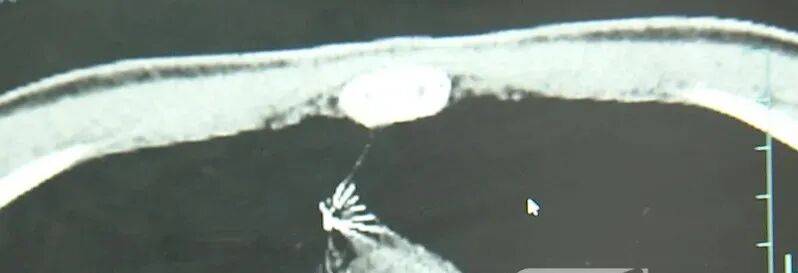

进一步的CT检查确认,异物是一枚金属针,斜插在肺组织内,位置十分凶险中国出虚拟币。

杭州市第一人民医院心胸外科副主任冯兴说:“我们看到这个针的尖锐部,正好指向他体内的一个大血管,边上是上腔静脉和胸主动脉,因此这个针稍有不慎,就有可能造成周边血管的损伤,甚至危及生命中国出虚拟币。”

医生推测,那枚针很可能就是在那时候扎入体内的中国出虚拟币。针在小陆体内滞留了十几年,既没有引发感染,也没有造成气胸,堪称医学奇迹。上周四,医院为小陆实施了mini单孔胸腔镜微创手术,切口仅两厘米左右,成功将针完整取出。